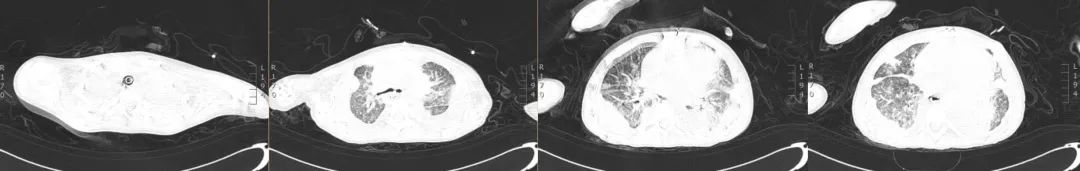

经过临床-康复-护理积极地综合治疗与管理,影像学对比发现:双肺弥漫性渗出灶较前明显吸收,双侧斜裂积液及心包腔内积液稍减少。

图:2019年5月5日CT

图:2019年6月10日CT